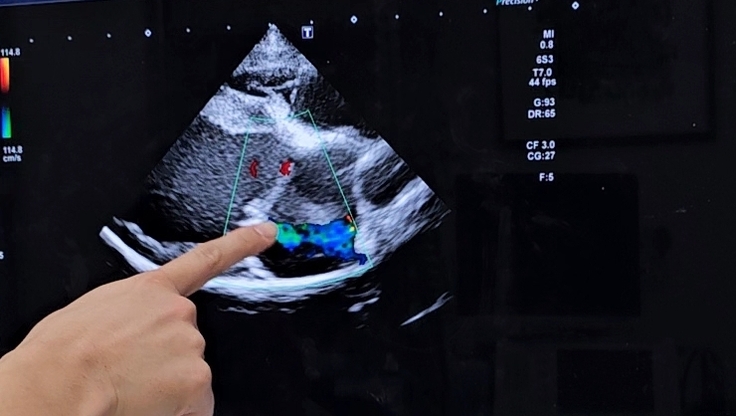

結果は少し心臓縮んでいましたがやはり逆流は弁の中心から出ていました。

緑色の所が逆流しています。

動画で撮っていたので途中でスクショで載せています。

前回より小さくなっているもののやはりまだ大きいみたいで、弁の中心が一番最後に止まるみたいなのでやっとここまでこれたけど、まだまだ小さくして逆流を止めていく為にお薬は1日3錠を飲んでいます。

朝陽の心臓の大きさが31ミリで、今の7割位が本来の大きさらしいですがここからが勝負ですね。